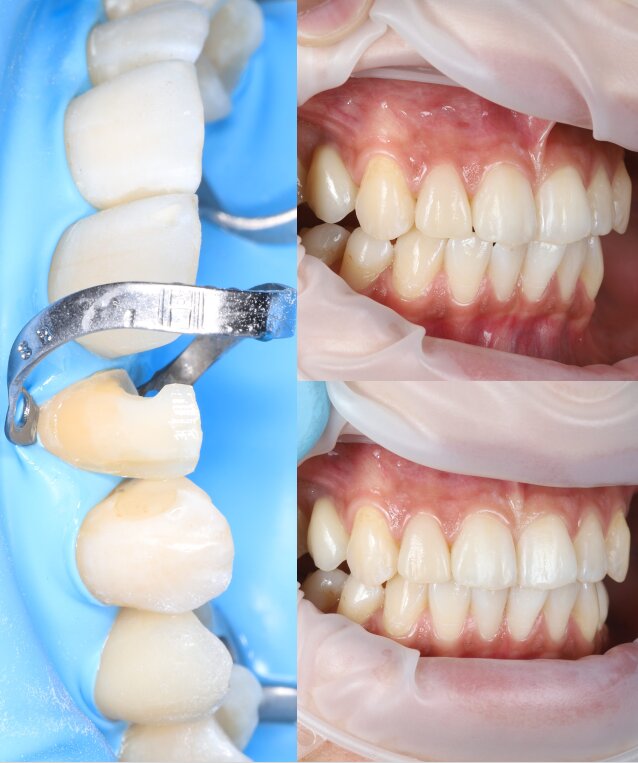

Портфоліо лікаря

У портфоліо представлені реальні клінічні випадки з практики лікаря — від первинного стану до результату лікування. Кожен кейс демонструє індивідуальний підхід, сучасні методи лікування та увагу до деталей